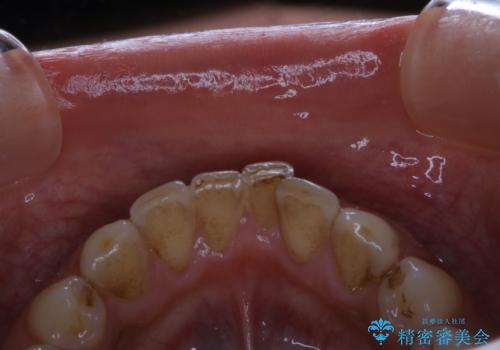

- 毎日コーヒーを飲むため、歯の着色がとっても気になるとのことでした。歯科でのクリーニングは2.3年ぶりのため全体的にきれいにしてほしいとのことでした。

PMTC60分コースを行いました。